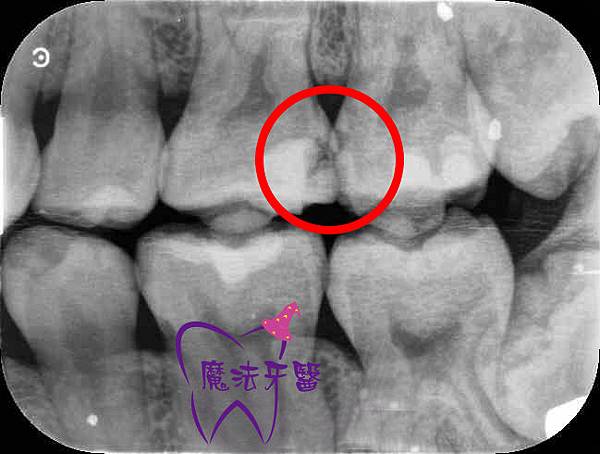

牙齿时,蛀牙往往不是用肉眼看口内就能观察出来,而是要透过x光片的

问:从x光牙片上是否能判断是否为继发龋. 2号牙齿补了

牙齿x光片怎么看蛀牙

牙齿x光片龋齿